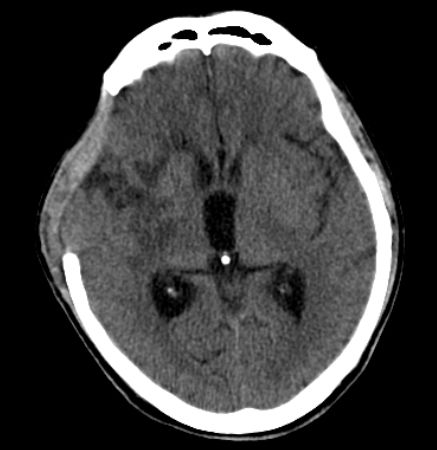

颅骨修补后头部影像。

完善术前相关检查排除手术禁忌症后,黄萌异主任医师团队于4月30日在全麻下为周某施行“自体骨颅骨修补、自体骨腹壁皮下取出术”。手术过程顺利,患者于术后第7天伤口拆线,5月8日康复出院。